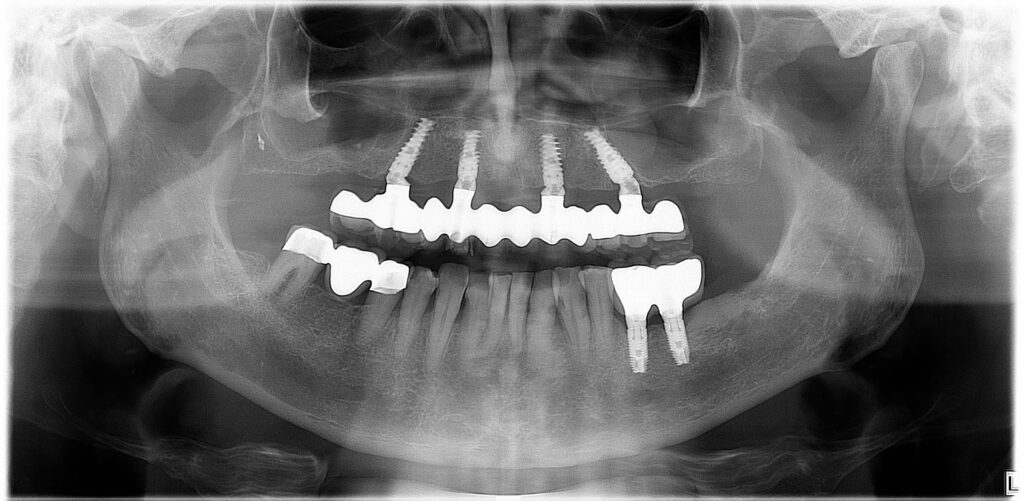

Ahogyan a képen is látható, az All-on-4 fogpótlás nem csak funkcionálisan, hanem esztétikailag is a legjobb megoldás teljes, vagy majdnem teljes foghiány esetében.

A fogászati implantátumok speciális szögben történő behelyezése miatt elkerülhető a csontpótló beavatkozás, így már maga a műtét, valamint a gyógyulás is gyorsabb.

A súlyos csontveszteség ellenére is sikerült páciensünknek fix, rögzített fogsort készíteni, a feslő állcsonton az All-on-4, míg az alsó állcsonton az All-on-6 implantációs megoldással, így visszakaphatta a rágás örömét.